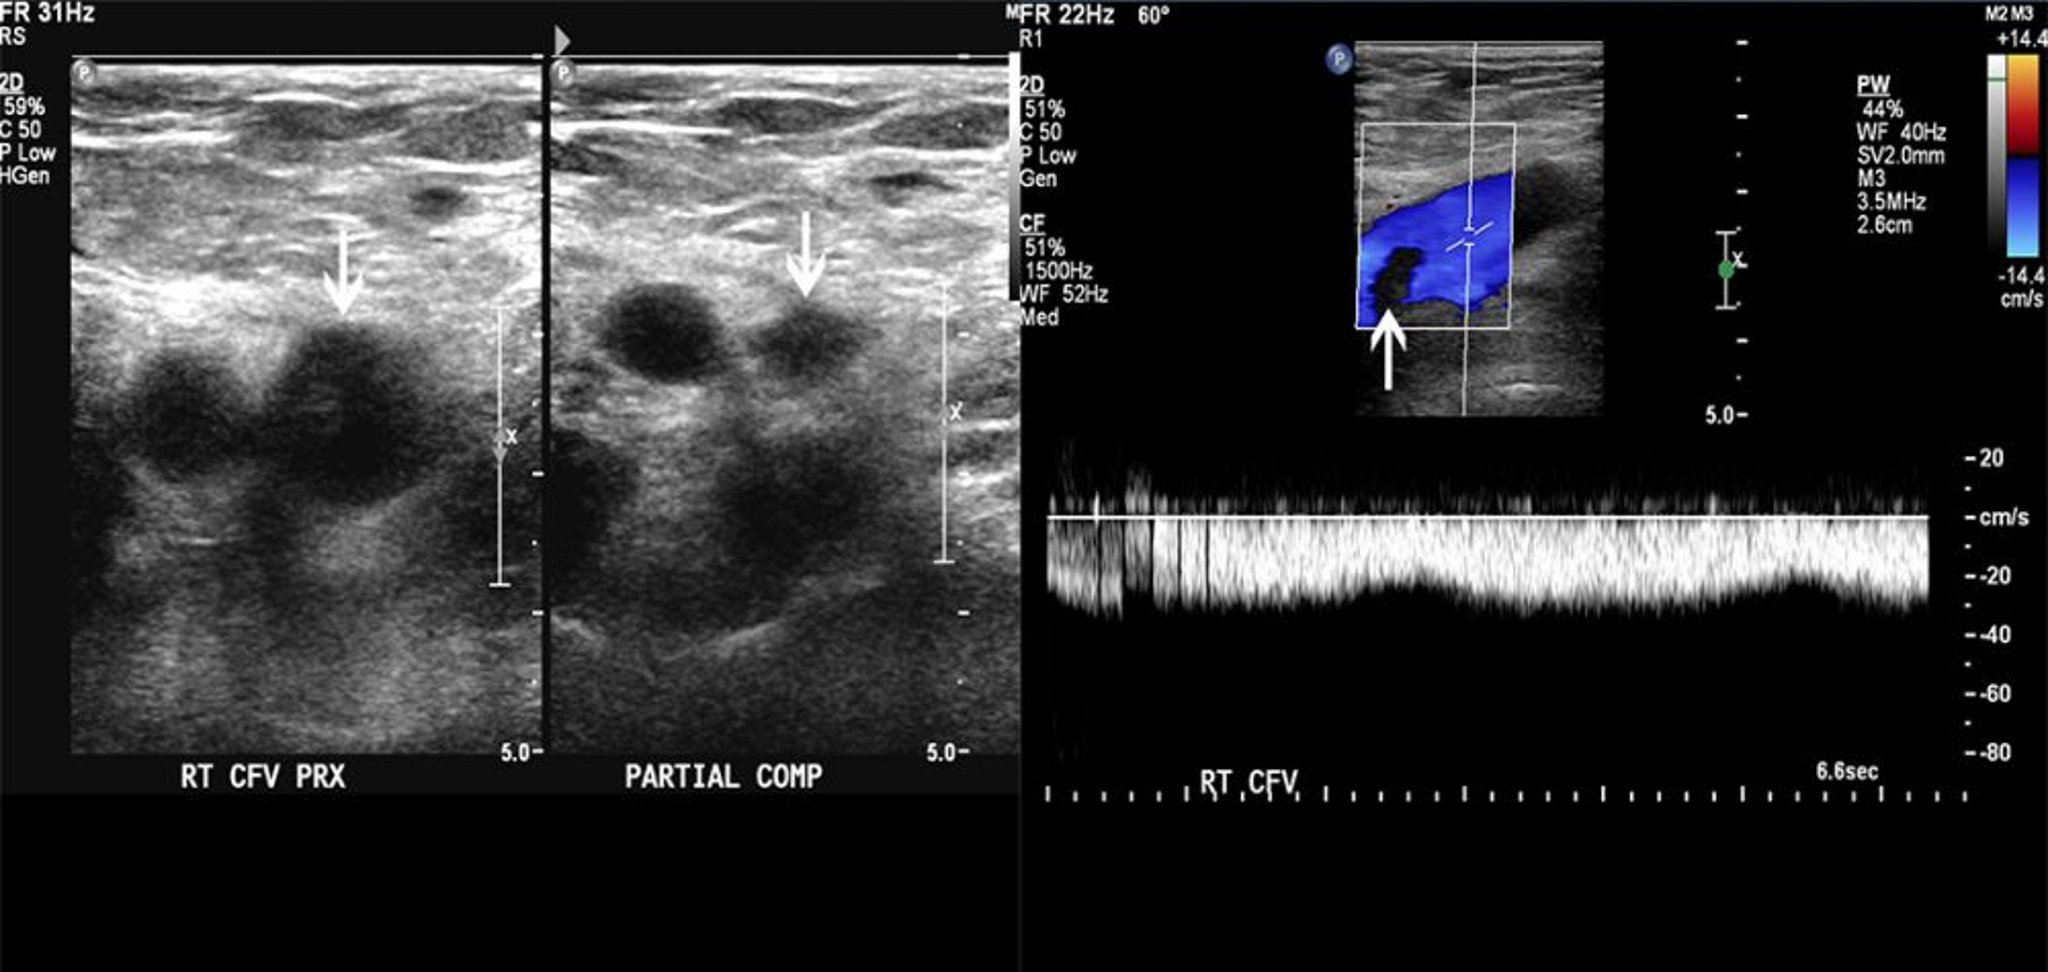

Siêu âm Doppler của một bệnh nhân có cục nghẽn trong tĩnh mạch đùi

Hình ảnh bên trái cho thấy khả năng nén một phần của tĩnh mạch đùi chung (mũi tên). Hình ảnh bên phải cho thấy một khiếm khuyết lấp đầy trên dòng Doppler màu. Những phát hiện này phù hợp với huyết khối.